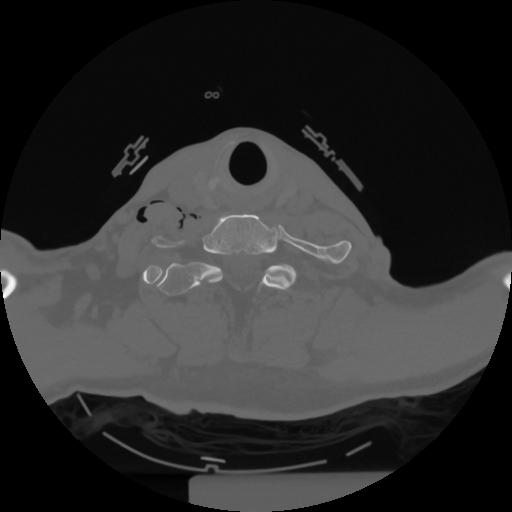

12 P.BLANDAS,,Vol,0.5,P.BLANDAS,,